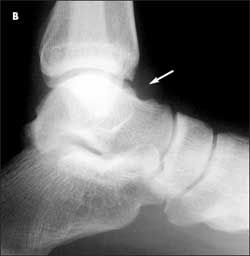

(Answer on next page.)Right ankle pain after a basketball injury: The frontal view of the ankle reveals soft tissue swelling that is predominantly lateral (A, yellow arrow). A small ossific fragment is evident distal to the lateral malleolus (A, white arrow); close inspection shows this to be well-corticated. The remainder of the osseous structures are intact. The lateral view reveals a joint effusion in the talotibial joint (B, arrow); no fractures are visible. In the oblique view (C), the osseous structures appear intact.

The well-corticated ossific fragment is consistent with an old injury, but it is in the region that is now extremely tender. The joint effusion indicates that the current injury is severe. However, this is a nonspecific finding; joint effusions are seen with fractures and ligament and tendon injuries.

Because the patient’s pain is severe, you order an MRI scan to further evaluate the injury. A T2-weighted axial image reveals disruption of the anterior talofibular ligament (

red arrow).